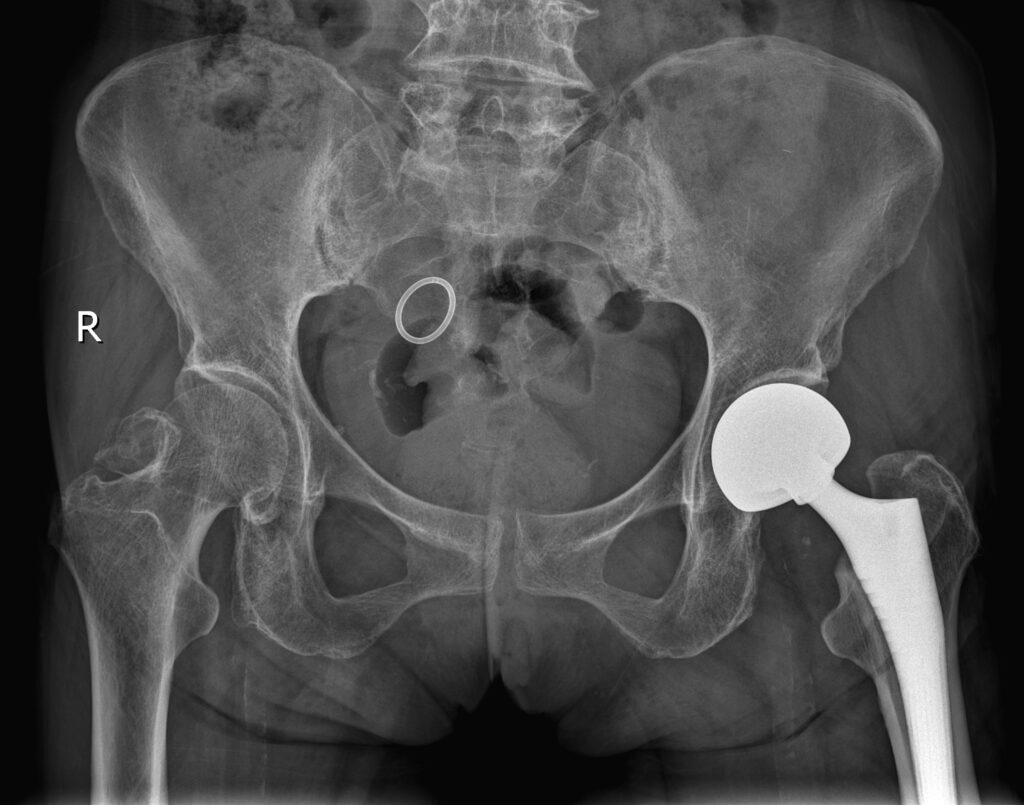

股骨颈骨折人工股骨头置换术(Artificial femoral head replacement for femoral neck fractures)